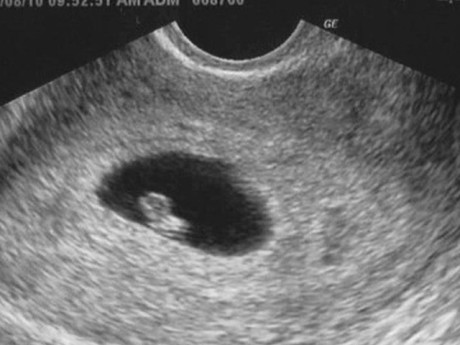

Khi bị sảy thai liên tục, nhiều chị em thăm khám mà không tìm được các nguyên nhân (Ảnh minh họa)